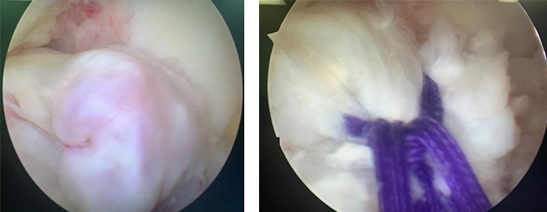

随后,张传开主任手术团队为强强进行了关节镜辅助下左胫骨平台骨折(胫骨髁间脊)复位固定术。术中,在关节镜辅助下对骨折块进行了复位。在复位固定的过程中,为了不影响孩子的发育,手术团队特意选用可吸收线进行固定,这种材料在术后半年至一年内可以被吸收掉,既不影响发育也能固定骨块,对孩子术后的康复来说比较好。

术中关节镜下资料